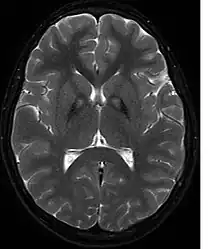

A neurological examination would show evidence of muscle rigidity; weakness; and abnormal postures, movements, and tremors. If other family members are also affected, this may help determine the diagnosis. Genetic tests can confirm an abnormal gene causing the disease. However, this test is not yet widely available. Other movement disorders and diseases must be ruled out. Individuals exhibiting any of the above listed symptoms are often tested using MRI (Magnetic Resonance Imaging) for a number of neuro-related disorders. An MRI usually shows iron deposits in the basal ganglia. Development of diagnostic criteria continues in the hope of further separating PKAN from other forms of neurodegenerative diseases featuring NBIA.

Microscopic features of PKAN include high levels of iron in the globus pallidus and the pars reticulata of substantia nigra, evident as a characteristic rust-brown discoloration[9] in a pattern called the eye-of-the-tiger sign;[10] lipofuscin and neuromelanin concentrated in the iron-accumulating areas; oval, nonnucleated structures representing swollen axons whose cytoplasm swells with vacuoles, referred to as spheroids, axon schollen, or neuroaxonal dystrophy; and Lewy bodies.[9]

Diagnosis of PKAN hit a milestone with the availability of MRIs, as well as the in-depth descriptions of those MRIs provided by Littrup and Gebarski (1985),[17] Tanfani et al. (1987),[18] Sethi et al. (1988),[19] Angelini et al. (1992),[20] Casteels et al. (1994),[21] and Malandrini et al. (1995).[22] The gene was localized to chromosome 20p by Taylor et al. (1996) [23] who suggested that this disorder should be referred to as neurodegeneration with brain iron accumulation (NBIA1) to avoid the objectionable eponym[24] of Hallervorden-Spatz. The disease was renamed 'pantothenate kinase-associated neurodegeneration' or PKAN by Zhou et al. (2001)[5] who suggested the name to avoid misinterpretation and to better reflect the true nature of the disorder. Most recently Pellecchia et al. (2005) published a report of 16 patients afflicted with PKAN, confirmed by genetic analysis.[25]